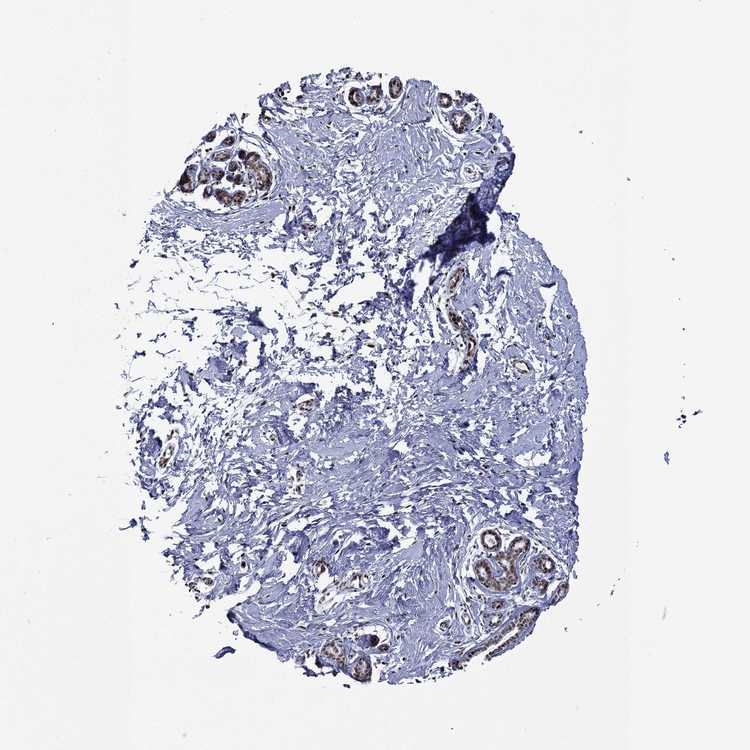

BREAST - Antibody stainingi

Antibody staining in the annotated cell types in the current human tissue is reported as not detected, low, medium, or high, based on conventional immunohistochemistry profiling in selected tissues. This score is based on the combination of the staining intensity and fraction of stained cells.

Each image is clickable and will lead to virtual microscopy that enables deeper exploration of all samples and also displays staining intensity scores, fraction scores and subcellular localization as well as patient and tissue information for each sample.

Antibody HPA006714Antibody CAB079946Antibody CAB079947

Adipocytes LowNot detectedNot detected

Glandular cells HighHighHigh

Myoepithelial cells MediumHighHigh